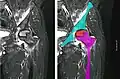

Radiography of avascular necrosis of left femoral head. Man of 45 years with AIDS. -

Nuclear magnetic resonance of avascular necrosis of left femoral head. Man of 45 years with AIDS. -